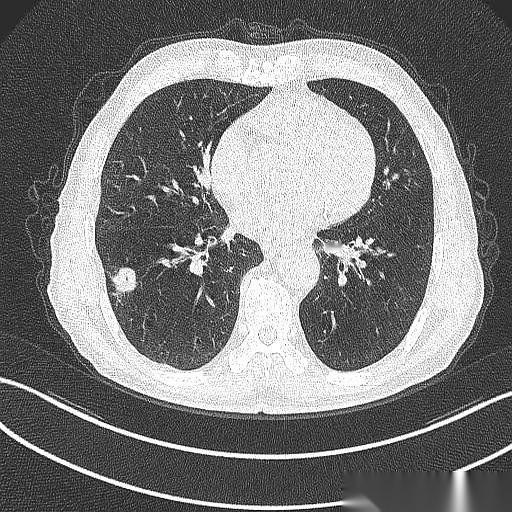

肺鳞癌,手术切完9年了,人活得好好的。 最绝的是,这大爷手术后烟都没戒。 真的,就是少抽了点。 说起来也邪门,当初救了他一命的,竟然就是他那要命的咳嗽和胸闷。要不是这俩症状把他折腾得受不了,跑去医院拍了个片子,那个藏在肺里2.4厘米的坏东西,还不知道要逍遥到什么时候。 一个抽了40年烟的71岁老爷子,你想想那犟劲儿。 手术很成功,切下来一看,万幸,早期,淋巴也没事。按理说,这都鬼门关前走一遭了,总该惜命了吧? 人家偏不。 就这么吊儿郎当地,九年过去了。 每年复查,啥事没有,肿瘤连个鬼影都见不着。有时候你真的会怀疑,老天爷是不是也有自己的KPI,专门考核戏剧性。 但命运这东西,总爱在结尾给你来个回马枪。 癌是没了,肺气肿倒是越来越厉害了。CT片子上,那肺啊,被烟熏得千疮百孔的。 老爷子今年终于又提了,说,准备戒烟。 也不知道这次是不是真的。 你说这人啊,有时候命硬得像块石头,有时候又犟得让人哭笑不得。 躲得过阎王爷,却好像总躲不过自己亲手点燃的那根烟。